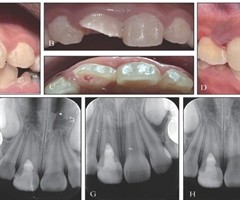

牙髓组织应对牙外伤的生物学反应及相关临床诊疗策略

[摘要]牙外伤在口腔临床治疗中极为普遍,不同类型和程度的牙外伤能触发牙髓组织的一系列生物学反应。有效评估牙髓状况并采取适宜的治疗措施,对于预防牙髓并发症,促进年轻恒牙牙根持续生长,以及最大限度地保留天然牙齿至关重要。本综述综合探讨了牙外伤引...